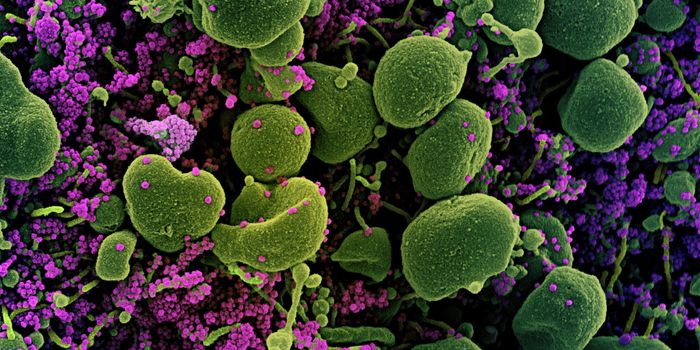

SEP 28, 2020Genetics & GenomicsSince the start of the pandemic, scientists have been trying to find out why some people get such severe illness from SA ...

APR 20, 2020Cell & Molecular BiologyThe SARS-CoV-2 virus causea huge range of symptoms, and researchers are learning more about the worst cases, which may h ...